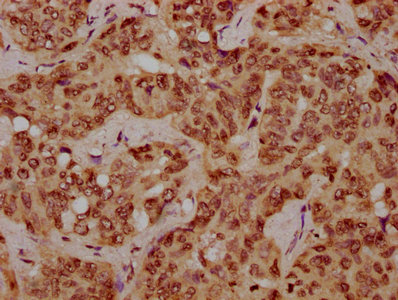

• IHC image of CSB-PA010378OA116nhibHU diluted at 1:10 and staining in paraffin-embedded human liver cancer performed on a Leica BondTM system. After dewaxing and hydration, antigen retrieval was mediated by high pressure in a citrate buffer (pH 6.0). Section was blocked with 10% normal goat serum 30min at RT. Then primary antibody (1% BSA) was incubated at 4°C overnight. The primary is detected by a biotinylated secondary antibody and visualized using an HRP conjugated SP system.